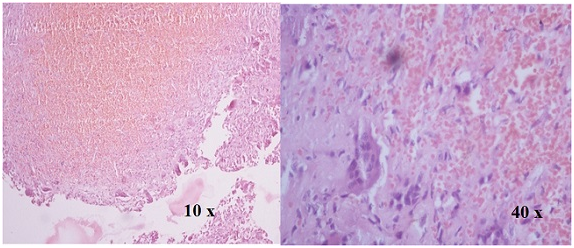

Figure 2 H&E Stained section show large osteoclast like giant cells and uniform ovoid mononuclear cells (Giant Cell Tumor).

Figure 3 H&E Stained section show osteoclast like giant cells , mononuclear malignant cells and malignant osteoid (Giant cell rich Osteosarcoma).

Figure 4 H&E Stained section show spaces separated by septa containing blood. Septa compose of osteoclast like giant cell and fibroblast  (Aneurysmal bone cyst).

Figure 5 H&E Stained section show osteoclast like giant cells in cluster and mononuclear cells are loosely arranged and mainly in spindle shape (Giant cell reparative granuloma).